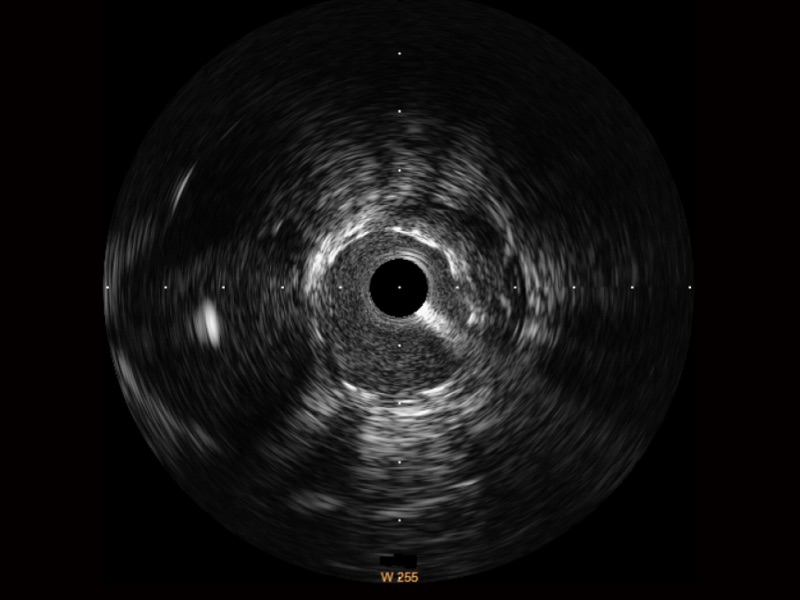

传统IVUS图像

对比传统IVUS导管成像,美狮贵宾会官网宽频IVUS图像的近场支架梁显影更细腻,远场中膜外血管仍清晰可辨,兼顾远中近,兼顾分辨力与穿透深度